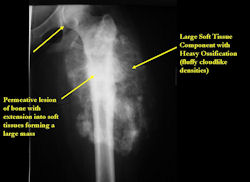

Radiographic Presentation: Conventional Osteosarcoma

There are 3 radiographic presentations for osteosarcomas, depending upon the amount of osteoid/ossification and calcium deposition:

- Mixed sclerotic and lytic, permeative lesion most common radiographic presentation

- Purely osteoblastic, permeative lesion: dense sclerosis and osteoid production

- Purely lytic, permeative lesion: little osteoid production and/or minimal calcium deposition in osteoid

Conventional osteosarcomas are permeative lesions on plain radiographs (borders of the lesion cannot be clearly delineated)

- Wide zone of transition from lytic/sclerotic areas of tumor to normal bone

- Makes borders of lesion hard to define

- Most (90%) arise from the metaphysis of the bone

- Rarely (10%) arise from the diaphysis

- Most conventional osteosarcomas (90-95%) extend through the bone into the soft tissues and form a soft tissue mass outside of the bone